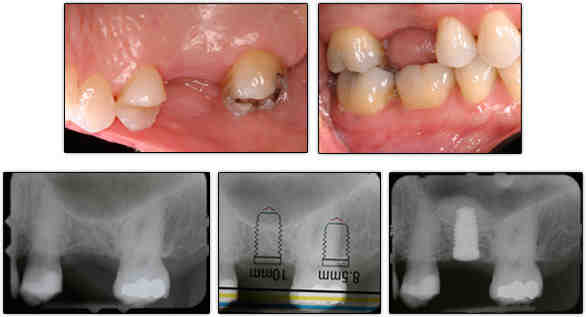

Do dental implants always require bone grafts?

Bone grafting is not always necessary for the placement of dental implants, but in cases where this procedure is indicated, it can help to significantly improve the patient’s chances of good treatment results. Only your surgeon can determine the need for a bone graft, often using special imaging technology.